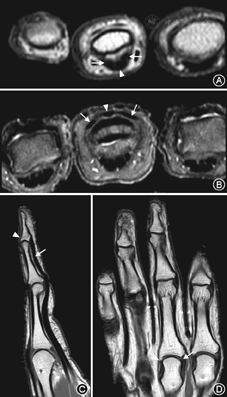

20名正常志愿者的手指肌腱韧带结构在MR图像上均表现为细条状均匀低信号,肌纤维连续(图3)。侧副韧带在冠状位显示最佳;中央束、矢状束、末端腱及屈肌腱在矢状位和轴位显示最佳。

50例手指外伤患者中,侧韧带损伤患者33例,伸肌腱损伤10例,屈肌腱损伤4例。其中有8例在肌腱韧带损伤的同时伴有指骨或掌骨骨折。损伤的韧带及肌腱在T1WI序列表现为肌纤维增粗模糊、部分或完全不连续,PD-FS序列信号不均匀增高,纤维中断,其内可见水样高信号,损伤周围可见软组织水肿(图4,图5)。手指MR影像对比度和信噪比良好,屈伸肌腱和侧副韧带等主要结构显示清晰,可以满足影像诊断的需要。